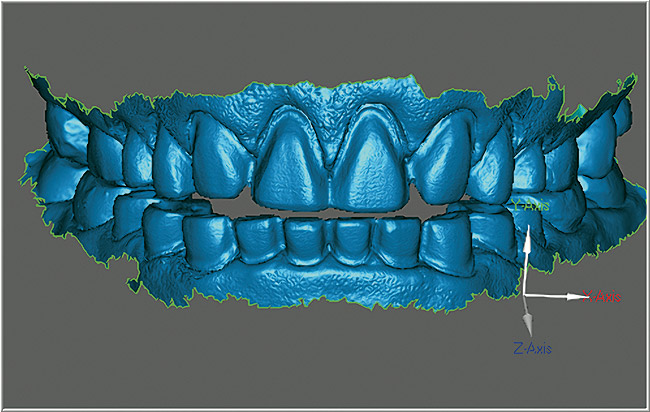

După finisarea preparaţiilor, retracţia s-a obţinut utilizând o pastă de retracţie gingivală. Materialul solid disponibil în seringă este simplu de folosit şi delicat faţă de ţesutul gingival. După aplicarea unui strat subţire de pulbere de contrast, s-a utilizat un aparat de scanare orală pentru a captura cu precizie extremă amprentele digitale ale preparaţiilor, cu o rezoluţie crescută, alături de înregistrările ocluzale.17 Acest sistem este unic datorită utilizării tehnologiei de capturare video tridimensională şi permite utilizatorului să verifice dacă toate componentele critice ale amprentei sunt obţinute prin simpla monitorizare a ecranului în cursul capturării. Se pot, de asemenea, revizui marginile individuale ale preparaţiei pentru deplinătate şi detalii (fig. 5).

Este necesară doar o retracţie minimă, deoarece toate marcajele marginale, gravajul şi secţionările se efectuează virtual. În pus, procesul de prescriere este complet automat, iar informaţiile se introduc simplu pe un monitor de tip touchscreen. Fişierul se trimite apoi prin email pentru procesarea modelului.

Spre deosebire de amprentele tradiţionale din polivinil-siloxan (PVS) în care toţi dinţii restauraţi trebuie retractaţi şi izolaţi în acelaşi timp, aparatul de scanare orală permite capturarea, la nevoie, a secţiunilor. După finalizarea amprentării digitale, în câteva zile modelele SLA răşinoase se recepţionează de laborator, se aplică pinuri, se secţionează şi sunt pregătite de montare şi fabricarea restaurărilor restante (fig. 7).